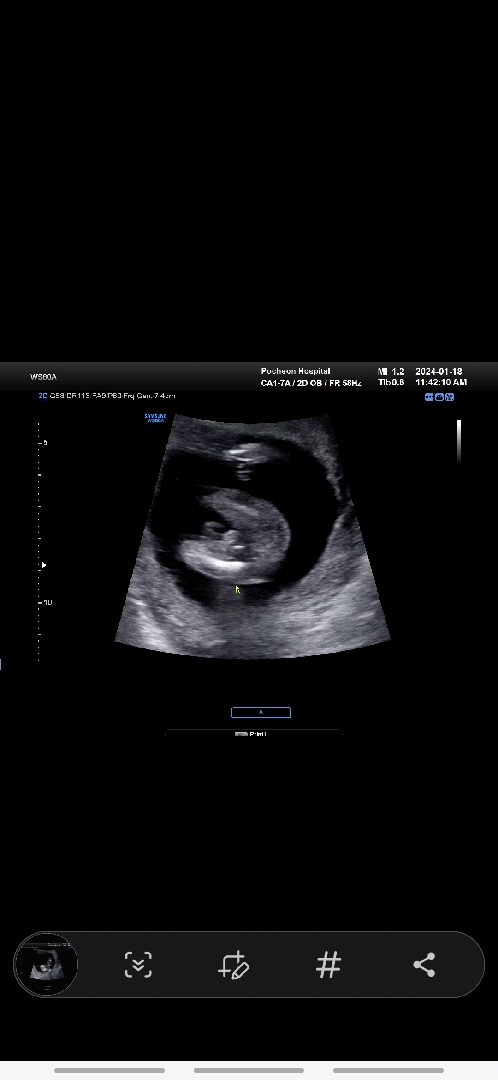

15주1일차 성별 봐주세요!

의사선생님께서는 탯줄같다구 하셨는데 아들 같아서요~ 아들은 다리사이가 저렇게 동그랗게?튀어나오는게 맞나요?

조카들 초음파를 많이 본 사람으로 봤을땐 탯줄같아여!아들은 다리 사이에 뾰족하게 튀어나와있더라구요ㅋㅋ